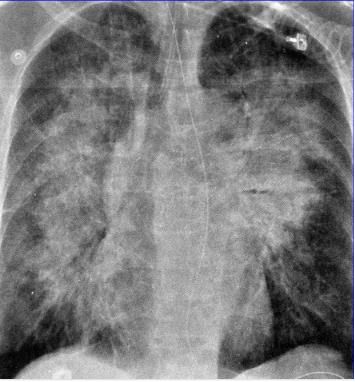

蝶翼征是什么样的?

下图是非常典型的蝶翼征。